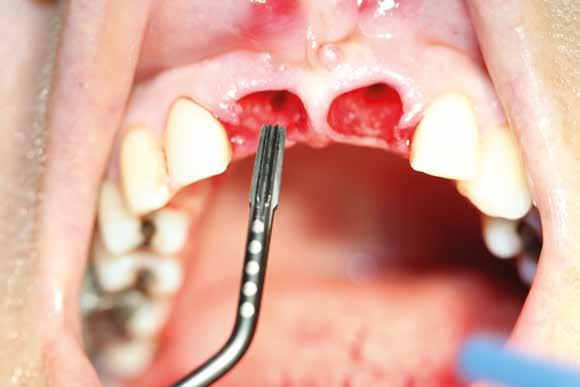

Alla visita di rivalutazione è emerso un ulteriore peggioramento della situazione, confermata anche dall’esame radiografico, con parodontopatia, sanguinamento al sondaggio, infiammazione diffusa, alitosi, difetto parodontale verticale mesiale a 2.3, residui radicolari 1.4, 1.6, 1.7, 3.6, 3.8 e carie destruenti di 1.5, 2.6, 3.5, 3.7 (con lesione endoperio) e 4.7 con estrusione e carie (Figg. 1, 2)

L’esame CBCT ha rivelato un quantitativo di osseo sufficiente a procedere con l’intervento implantare, anche se erano ancora visibili le zone delle estrazioni; inoltre ha evidenziato una lesione osteolitica a carico del 3.5 che abbiamo dunque deciso di estrarre (Figg. 7-20).